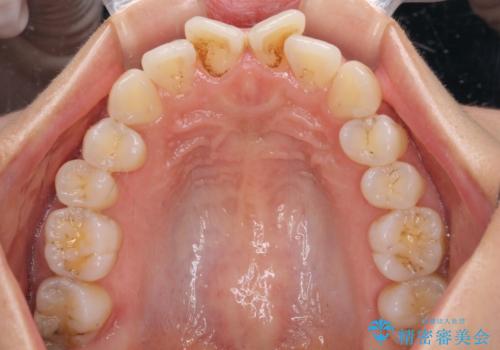

- 捻れた前歯が飛び出しており、口が閉じにくいとのことで来院された患者様です。

出っ歯というわけではないものの、前歯の捻転により口唇が押し出されている状態でした。

親知らずを抜去し、歯列全体を後方に移動させつつ、IPR(歯と歯の間を削る)でスペースを獲得し、インビザラインを用いて叢生を解消しながら前歯の突出を改善することとしました。

骨格的に上下正中がずれていたため、奥歯がしっかりと噛み合うか心配でしたが、ずれているなりに、しっかりとした咬み合わせとなりました。